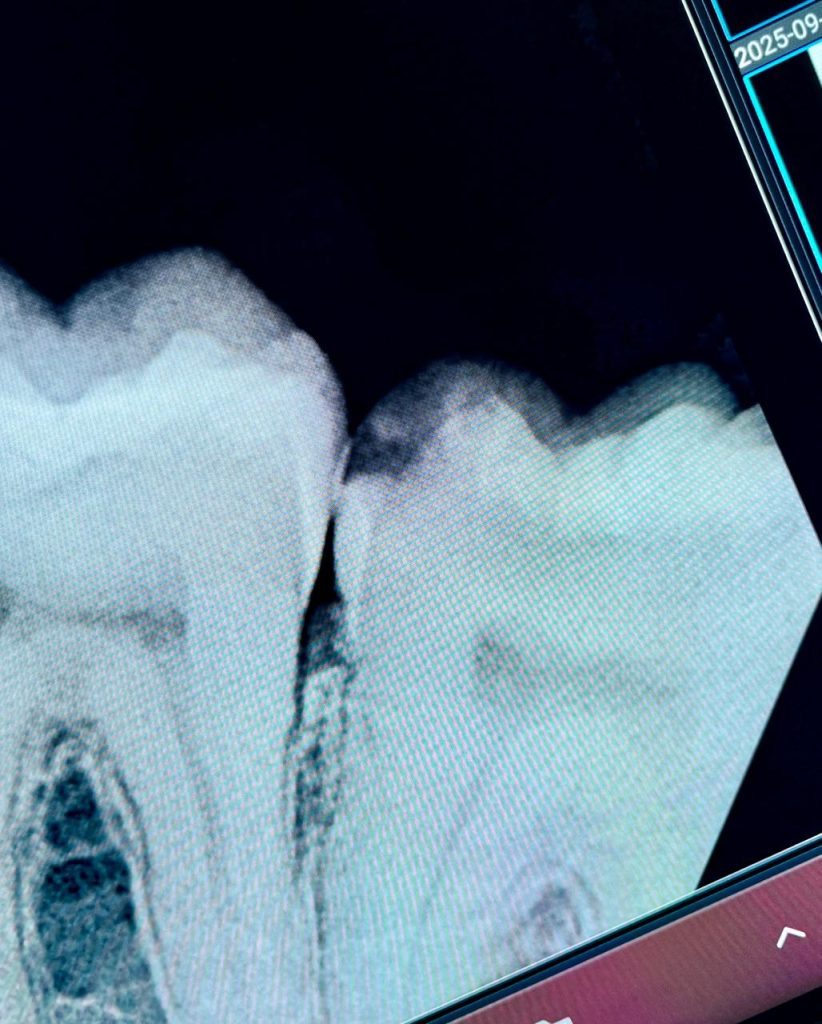

A 1 mm base layer of GC EverX Flow (fiber-reinforced flowable) was placed to mimic dentin and control polymerization stress. The short fibers provided fracture resistance and internal support for the onlay build-up (Fig 4).

- Fig 4: GC EverX Flow base for dentin replacement.